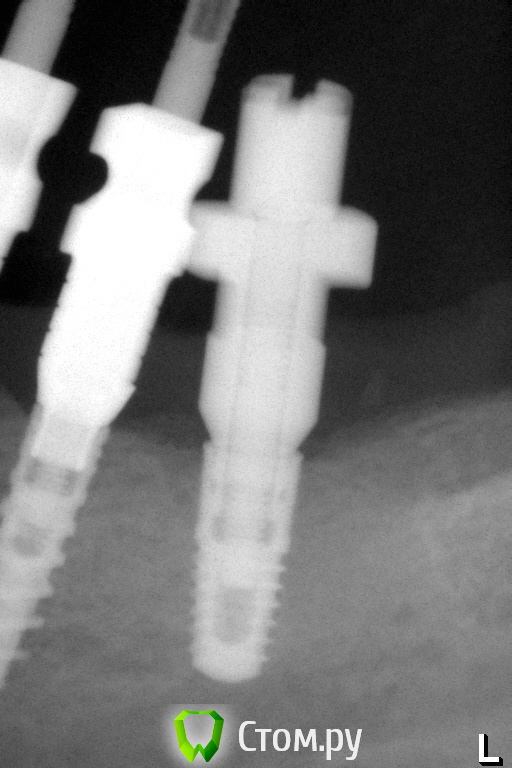

Pavel-Pskov Опубликовано 4 ноября, 2014 Автор Поделиться Опубликовано 4 ноября, 2014 Еще пара снимков.Через год. Ссылка на комментарий

syrovovec Опубликовано 4 ноября, 2014 Поделиться Опубликовано 4 ноября, 2014 В Adin NP вроде как конусное соединение? Ссылка на комментарий

pigmaleon Опубликовано 4 ноября, 2014 Поделиться Опубликовано 4 ноября, 2014 В Adin NP вроде как конусное соединение?нет, шестигранник 1 Ссылка на комментарий

doca Опубликовано 4 ноября, 2014 Поделиться Опубликовано 4 ноября, 2014 нет, шестигранникнет ,конус 1 Ссылка на комментарий

doca Опубликовано 4 ноября, 2014 Поделиться Опубликовано 4 ноября, 2014 Какие-то странные абатменты, как-будто в имплантаты заходят на 1мм.техник ,по ходу, подрезал их зачем-то. может быть там винтовая фиксация с вклейкой Ссылка на комментарий

Pavel-Pskov Опубликовано 6 ноября, 2014 Автор Поделиться Опубликовано 6 ноября, 2014 техник ,по ходу, подрезал их зачем-то. может быть там винтовая фиксация с вклейкойДа. Ссылка на комментарий